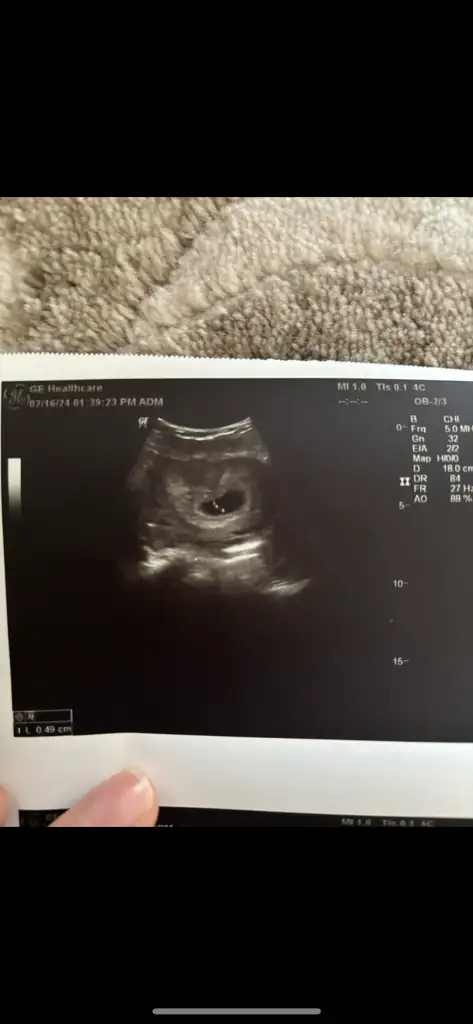

Kızlar iyi geceler hepinize. Bugün ilk kontrolüme gittim kalp atışını duyduk adet tarihim ile uyumlu çıktı. 6+2 dedi progestan verdi ağrım çok var diyince.

Mide bulantısı hiç bir şey yok bende sadece kasık ağrım çok fazla